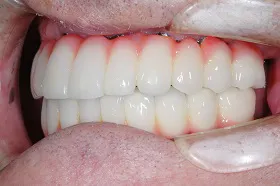

全ての歯をインプラントで治療したケース

上下ともに総入れ歯の患者様が来院され、「入れ歯ではなく、自分の歯のように何でも噛めるようにして、美味しく食事がしたい。」とおっしゃいました。

■治療前

■治療後

■治療中レントゲン写真

患者様と相談して、入れ歯のように取り外すことなく、固定式で治していく事に決めました。上下にインプラントを8本づつ埋め、白い歯をかぶせるようにして治療しました。

「お正月に、何年ぶりかでおもちを食べることができました。」と患者様に言われ、非常に嬉しく感じた症例です。

| 主訴 | 上下ともに総入れ歯を使用 入れ歯が外れやすくて美味しく食事ができないので、しっかりと咬んで美味しく食事をしたい |

|---|---|

| 治療方法 | インプラント治療 |

| 治療期間 | 約1年 |

| 通院回数等 | 15回位 |

| 費用 | 約680万円 |

| リスク・副作用 | インプラント術後の腫れ・痛み |